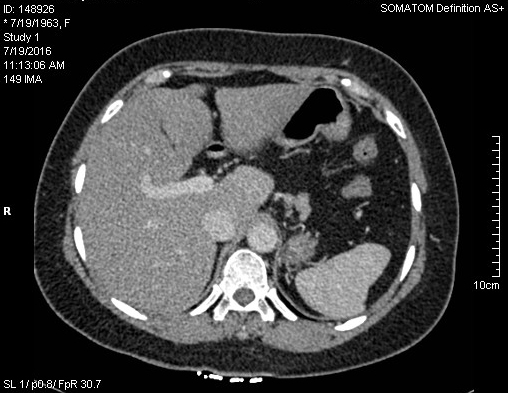

La CT scanner de l'abdomen du

tube digestif et des voies biliaire :

La Tomodensitometrie computerisation

( CT scanner ) simple se base sur la

balayage d'une faisceau de rayon x sur le patient en plusieures de angles inclinees sur une

meme plan de coupe . Les signales a receuillir par detecteur de rayon

X a

cote opposee du faisceau , seraient traites en informatique

numerique a aide d'outils mathematiques ( algorithmes) ce

qui permettre de recontruire en image un coupe anatomique .

Cette methode est plus couteuse que echographie mais est

l'examen de deuxieme intention pour exploration de la

pathologie du foie , des voies biliaires et de pancreas

. Sa resolution et image de receuillir etre bien et sa champ

de visuelle est plus large que echographie .Ce qui ainsi

peut utilise de recherche de adenopathie et de extention

locale ou metastasique de cancer de voie biliaire .

...Recontruction multiplanaire

et resolution spaciale en trois plans pour explorer et les

coupes doient fine de moins 3mm a low dose . L'etude du grele par CT scanner necessite un opacification

des anses intestinales par produit de contrast a ingestion

simple par la bouche : enterographie avec tomodensitometrie

ou intillation par sondage : enteroclyse avec scanner .

Diagnostic des pathologies du grele se met sur etude de

epaisseur de la paroi du grele ou de defaut de remplissage de

la lumiere intestinale .

| |

|

Coupe axiale de estoma (

normale ) |

Coupe axiale de estoma ( ulcere ) |

images enteroclyse +scanner |

L'indication de CT scanner digestive

sont vastes : ils sont necessaire pour un grand nombre de

pathologies digestive , les lesions inflamatoires , tumorales ,

traumatiques , vasculaires ou mecaniques. Et encore a aide du CT

scanner tous les organes pleines abdominaux , les vaisseaux

, les aires ganglionaires et la graisse intra abdominale

sont en meme de explore . La tomodensitometrie helicoidale : combinant

la rotation continue des detecteurs du tube de rayon X avec

un deplacement longitudinal du patient , ce qui permet

acquisition en quelques seconds d'un volume de lesion .

L'Indication de TDM de voie biliaire permet

en resume : L'ocalise l'obstacle et oriente

l'etiologie , recherche et caracteriser les lesions

tumorales volumeuse , qu'il soient benins ou maligns

ou des calcul hyperdense , Optimiser la technique pour detecte des

petite tumeurs ou des calculs isodenses

Contre indication de TDM : Allergie

au produit de contrast iode et insuffisance renale danms cas

TDM plus cointrast intraveineuse , la grossesse ( N'est pas absolue dans

la situation d'ủgence , contre indication relative

forte ) et cout est moyen

Image TDM du foie et de la

vesicule biliaire en coupe

axiale ( avec contrast iode intra veineuse ) . |

Image TDM en coupe

axiale a travers la vesicule biliaire ( avec

contrast ) . Vesicule biliaire sont en

voyait |